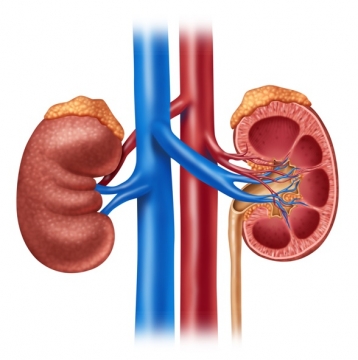

![]() NERKI (tekst i zadania)

NERKI (tekst i zadania)

„Było sobie życie – nerki”/”Det var en gang et liv – Nyrene”